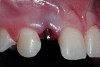

A 19-year-old non-smoking female presented for tooth replacement at the maxillary right and left lateral incisors, which were congenitally missing (Figure 1). The post-orthodontic result was adequate for the placement of 3-mm one-piece small-diameter implants. The preoperative radiographs can be seen in Figure 2 and Figure 3. The pretreatment clinical view in Figure 4 and Figure 5 shows the small intertooth space present in the lateral incisor areas. One of the most challenging tasks with congenitally missing lateral incisor cases is to create an acceptable soft tissue emergence profile from a crestal profile that is flat from the mesial of the canines to the distal of the centrals (Figure 4 and Figure 5). After pretreatment planning which consisted of a complete medical and dental history, radiographic analysis, and upper and lower study models mounted by a facebow transfer technique, the fabrication of a TempStent II surgical guide was completed. Figure 6 and Figure 7 show the occlusal view of the TempStent II guide on the study cast and in the oral cavity, respectively.